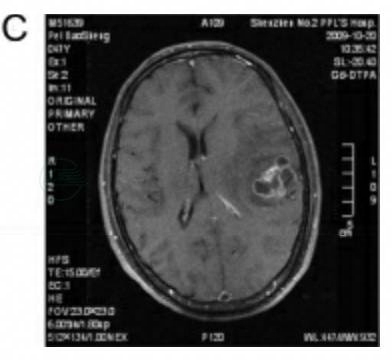

术后病理:左颞叶转移癌,肺癌转移可能性大(图6)。

图6 病例3病理切片

术后恢复良好,切口拆线后转胸科,纤维支气管镜活检确诊为小细胞肺癌,行化疗。